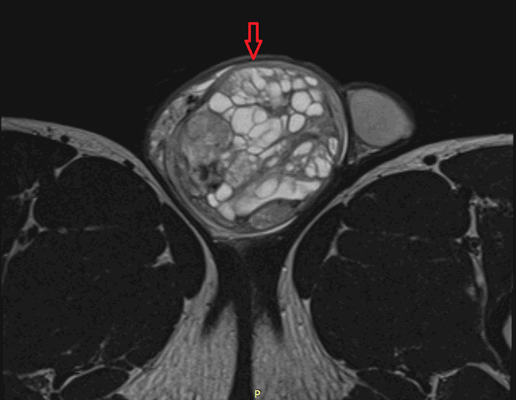

![Тератома яичника (УЗИ)]()

![Тератома яичника (МРТ)]()

Рисунок 3. – тератома яичника а –УЗИ, б — МРТ.